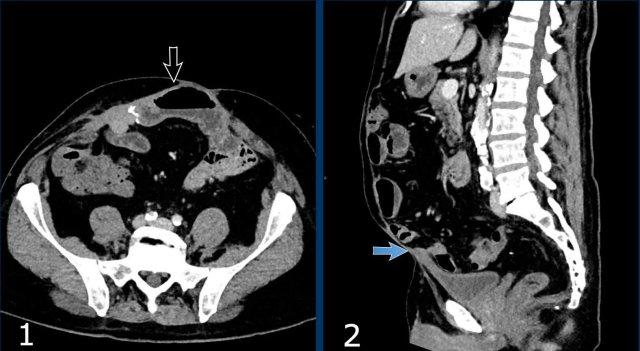

Ở bệnh nhân này với khối thoát vị, các số đo như sau:

- Thể tích túi thoát vị (HSV) = (203 x 85 x 125 mm x 0,52) x 10-6 = 1,12 lít.

- Thể tích khoang bụng (ACV) = (297 x 100 x 328 mm x 0,52) x 10-6 = 5,1 lít.

- Tổng thể tích phúc mạc (TPV) = ACV + HSV = 5,1 + 1,12 = 6,2 lít.

Mức độ mất vùng chứa = 1,12 / 6,2 x 100% = 18%